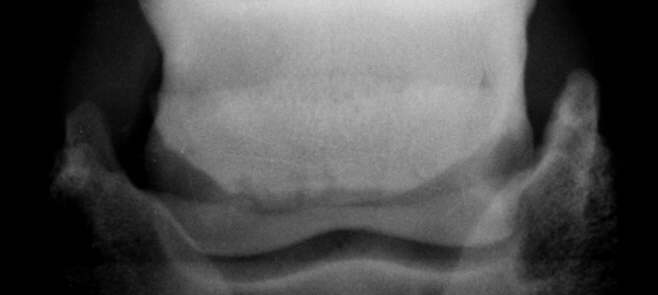

Deutlich ausgeprägte z.T. lollypopartig ausgebildete z. T. randständige Gefäßkanäle